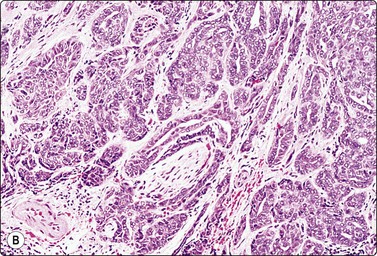

Malignant neoplasms

Acinic cell carcinoma (Figs 4.48-4.50)129,130

image image

Fig. 4.48 Acinic cell carcinoma

Epithelial fragments composed of cells with abundant vacuolated cytoplasm and relatively bland nuclei, resembling normal acinar cells; many naked nuclei; scanty, thin fibrovascular stroma. Note absence of well-formed acinar structures (A, MGG, IP; B, Pap, HP).

image

Fig. 4.49 Acinic cell carcinoma

Cells with oncocyte-like cytoplasm, distinction from oncocytoma difficult (MGG, HP).

Fig. 4.50 Acinic cell carcinoma

A less well-differentiated tumor may be difficult to type as acinic cell carcinoma. Ancillary techniques such as EM may help (MGG. HP).

Criteria for diagnosis

Abundant cell material with a clean background,

Cells mainly in clusters, scanty inconspicuous fibrovascular stroma,

Microacinar groupings,

Abundant, fragile, finely vacuolated, occasionally dense oncocyte-like cytoplasm,

Rounded, medium-sized nuclei, mild to moderate anisokaryosis, bland chromatin,

Many stripped nuclei.